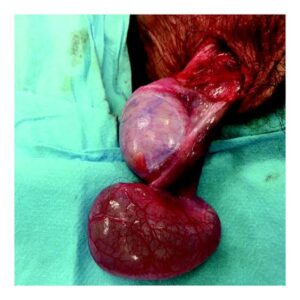

Read MoreHydrocele surgery

A fluid-filled sac around a testicle, often first noticed as...

Read MoreOverview